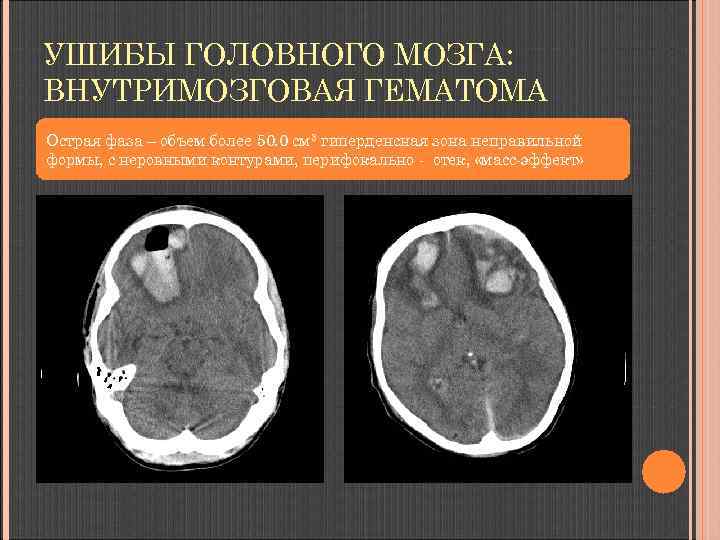

УШИБЫ ГОЛОВНОГО МОЗГА: ВНУТРИМОЗГОВАЯ ГЕМАТОМА Острая фаза – объем более 50. 0 см 3 гиперденсная зона неправильной формы, с неровными нечеткими контурами, перифокальный отек, «массэффект»

УШИБЫ ГОЛОВНОГО МОЗГА: ВНУТРИМОЗГОВАЯ ГЕМАТОМА Острая фаза – объем более 50. 0 см 3 гиперденсная зона неправильной формы, с неровными контурами, перифокально - отек, «масс-эффект»